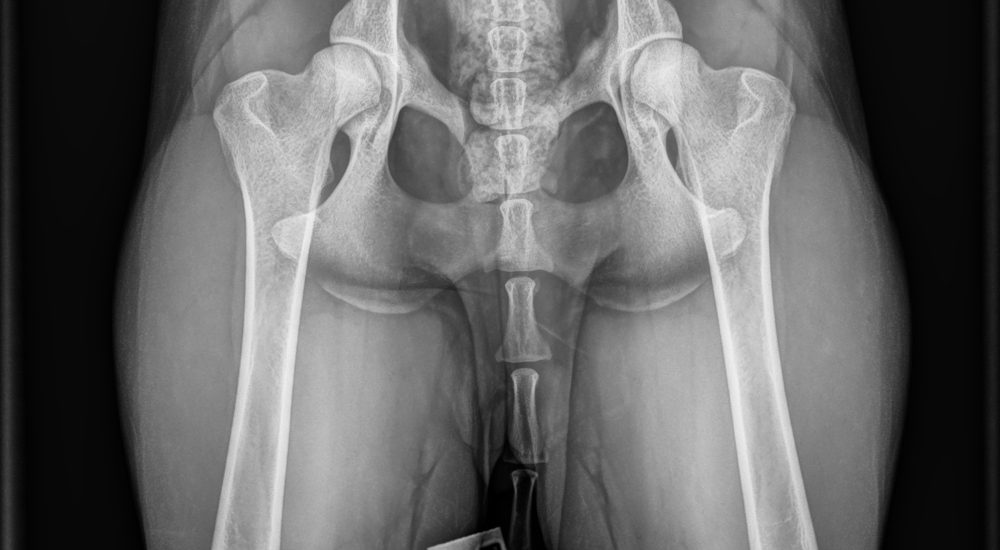

Lonkat 150 €

Lonkat + kyynärät 190€

Lonkat + kyynärät + selkä 300 €

Lonkat + kyynärärt + selkä + olat 330 €